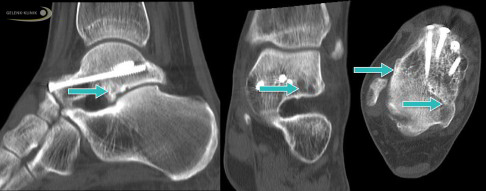

Die Röntgenuntersuchung zeigt bei einer Talusnekrose bereits charakteristische Veränderungen mit Aufhellungen des Knochens aufgrund der Demineralisierung.

Besonders hilfreich für die Untersuchung von Knochenveränderungen sind Schnittbildverfahren, die mit Röntgenstrahlung arbeiten. Neben dem Kernspin (MRT) und SPECT ist besonders die digitale Volumentomographie (DVT) des Sprunggelenks wertvoll, um die charakteristischen Veränderungen im Innern des Sprungbeins darzustellen.

Die Knochenszintigrafie ist durch ihre verschiedenen Aufnahmezeiten ebenfalls hilfreich. Sie hilft dem behandelnden Orthopäden, die Verteilung der Nekrose und auch die Risiken einer Frakturierung besser abschätzen zu können.

Nach einem Kollaps des Knochens unter dem Gelenkknorpel (subchondraler Knochen) kann nur das DVT (digitale Volumentomografie) die genaue Lage und Belastung der Knochenstrukturen darstellen. Das Röntgenbild als Überlagerungsbild ist ebenfalls eine gute Möglichkeit, die häufig aber – anders als die hochauflösende röntgenbasierte Schnittbilddiagnostik wie DVT oder CT – nicht die gesamte Situation der Strukturen darstellt. Daher ist ein Röntgenbild für eine Therapieentscheidung oft nicht ausreichend.